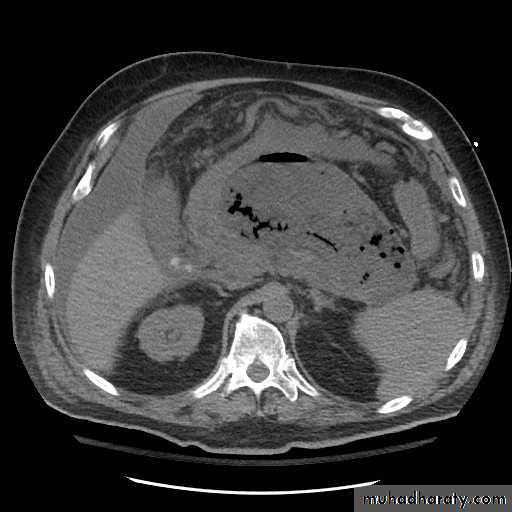

Chronic pancreatitis

Pancreatic carcinoma

Irresectable